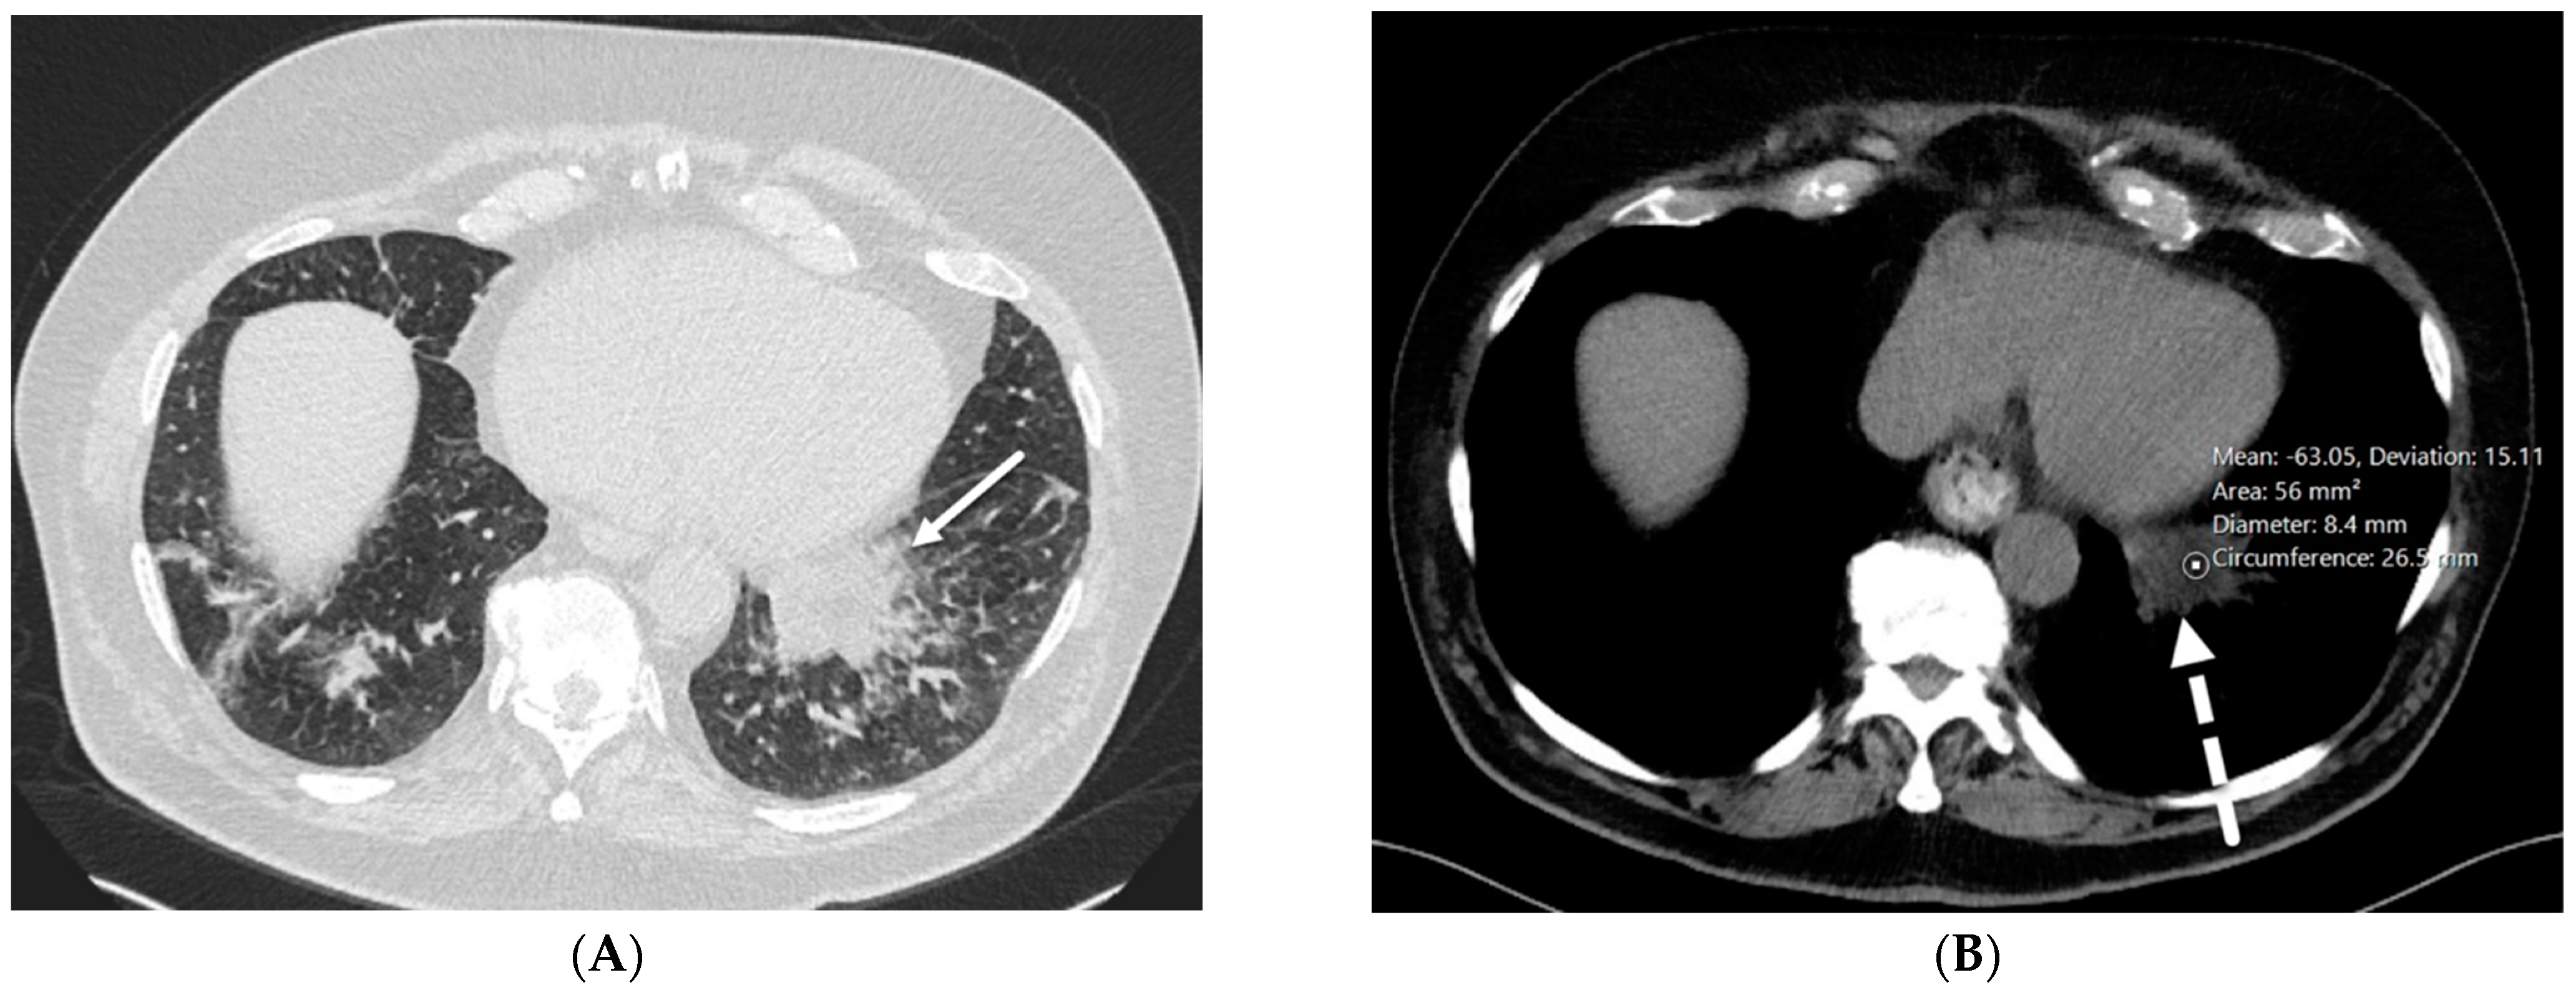

4.6. Silicone Embolization

4.7. Pulmonary Vein Stenosis (PVS)

7.2. Pulmonary Capillary Hemangiomatosis (PCH) and Pulmonary Veno-Occlusive Disease (PVOD)